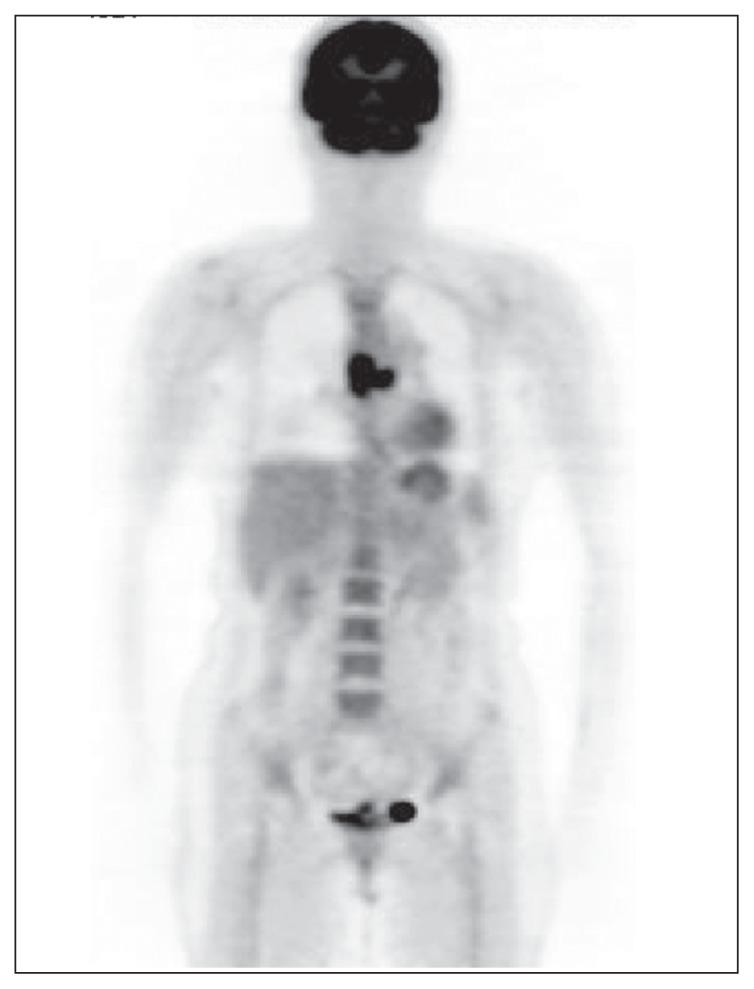

(18)F-FDG accumulations in primary malignant melanoma of the esophagus.

Surgery. 2006 Jul;140(1):118-9. doi: 10.1016/j.surg.2005.06.039.